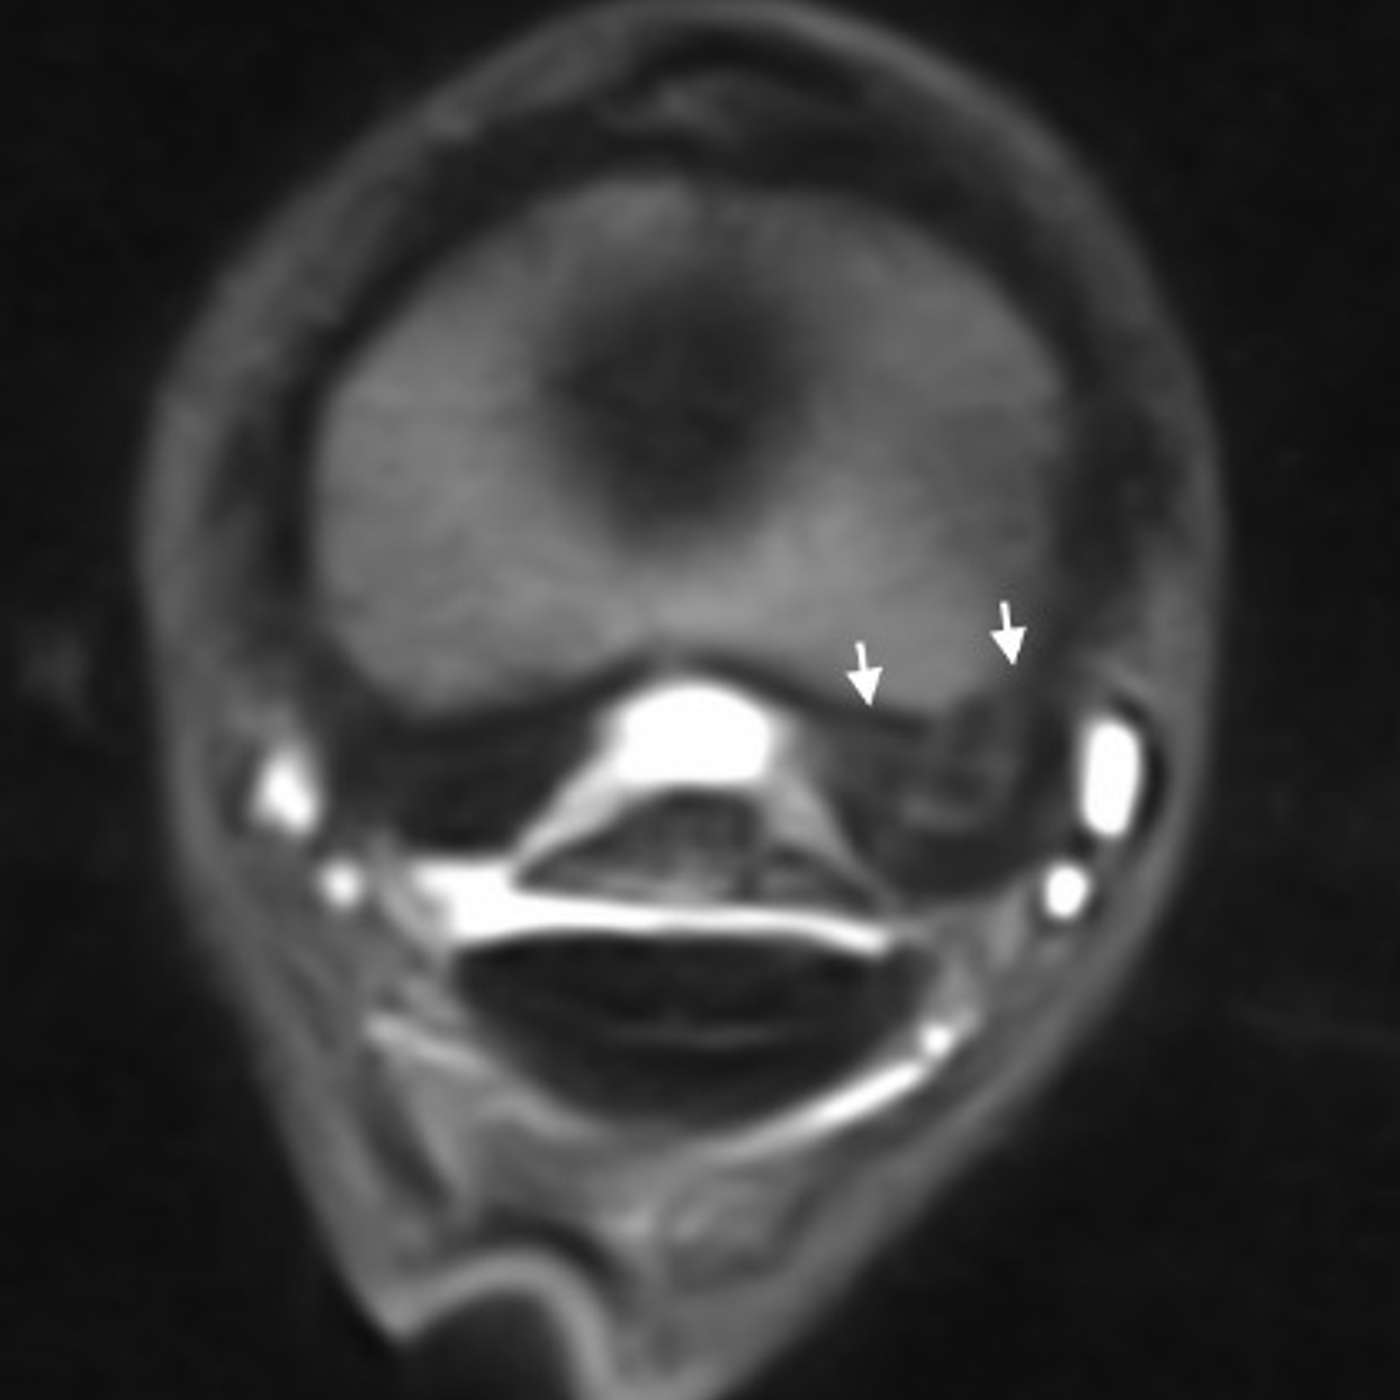

In this episode of The Hoofcare Companion, host Marc Jerram explores one of the most significant yet often misunderstood hoof injuries — pedal bone fractures. Joined by expert insights from veterinary and farriery perspectives, Marc breaks down how these fractures occur, how they’re classified, and the latest approaches to diagnosis, treatment, and rehabilitation. Listeners will gain a clear understanding of the vital role of radiography, therapeutic shoeing, and owner management durin...